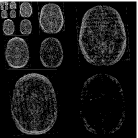

Note that term 2 is sparse if there are no major changes between and , both images have similar grey-level intensities and they are spatially matched. While these conditions meet in many application of dynamic imaging, such as prior image constrained compressed sensing (PICCS) in CT (Chen et al., 2008; Lauzier et al., 2012) and dynamic MRI (Jung et al., 2009; Lustig et al., 2006; Gamper et al., 2008; Yip et al., 2014), in longitudinal MRI none of these requirements are guaranteed. While there are solutions for miss-registration and variable grey level intensities (see Section 4), the temporal similarity in longitudinal MRI is a-priori unknown. Although longitudinal MRI may exhibit temporal similarity (Samsonov et al., 2010), we have to take into account that in many cases the follow-up scan may exhibit substantial changes with respect to the baseline scan. Such cases may occur, for example, if a surgical intervention was applied between the time points or if there is a major progressive or therapy response. Figure 2 shows two representative examples.

Baseline 4 months Baseline 3 months

Hydrocephalus GBM